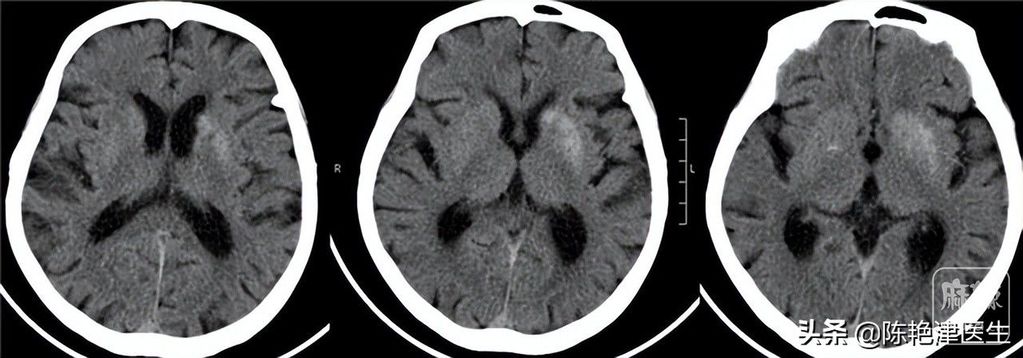

救护车来到后,先给徐大爷监测了生命体征,测量血压为109/58mmHg,徐大爷家人急救人员没有来到前监测的血压为163/89mmHg,说明徐大爷出现了很大的血压波动,疑似血栓脱落。 体温为35.2℃,体温下降符合脑梗患者昏迷症状,脉搏在55次/分,且脉搏呈下降趋势;呼吸频率在45次/分左右,出现下颌式呼吸倾向。 通过抽血化验发现血液中甘油三酯为6.2mmol/L,随后进行头颅CT,头颅CT发现梗死灶;通过DSA造影术直辅进行超选择介入动脉溶栓,溶栓剂为尿激酶,通过进行小剂量肝素静脉滴注。六个小时后,徐大爷渐渐恢复意识。